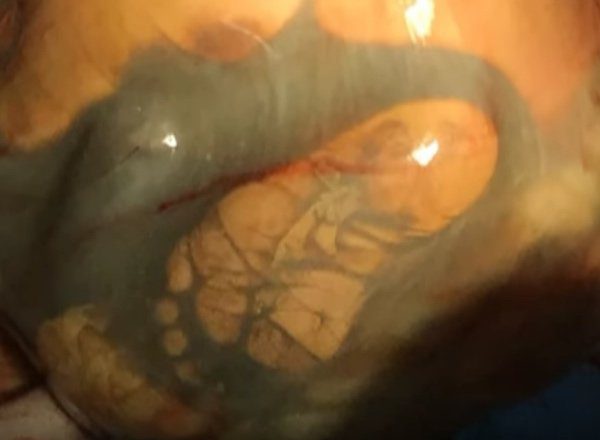

Az orvosok alaposan megvizsgálták a nőt, és alig hittek a szemüknek. A baba nem az anyaméhben, hanem a hasüregben volt – ezt nevezik méhen kívüli terhességnek, amikor a megtermékenyített petesejt a méh üregén kívül van. Az ilyen terhesség az anyát életveszélyes állapotba sodorhatja, és ha felmerül egy ilyen helyzet, akkor azonnali orvosi beavatkozásra van szükség.

Nagyon ritka az olyan esetek száma, ahol a csecsemő egészségesen kifejlődhet a méhen kívüli terhesség esetében. Ilyenkor az édesanyák csakis császármetszéssel hozhatják világra a gyermeküket.

A műtét ilyen esetekben nagyon kockázatos úgy az édesanya mint a gyermeke számára. A placenta eltávolítása végzetes vérveszteséget okozhat. Ebben az esetben a szülés csaknem két órát vett igénybe.

Amikor az orvosok eltávolították a magzatburkot az édesanya hasüregéből, csodának lehettek szemtanúi. A kislány teljesen kifejlődött, lélegzett és súlya több mint 4 kg volt. A büszke édesanya úgy döntött, hogy lányának egy különleges nevet fog adni, ezért Veronikának nevezte, amelynek jelentése győzelmet hozó.